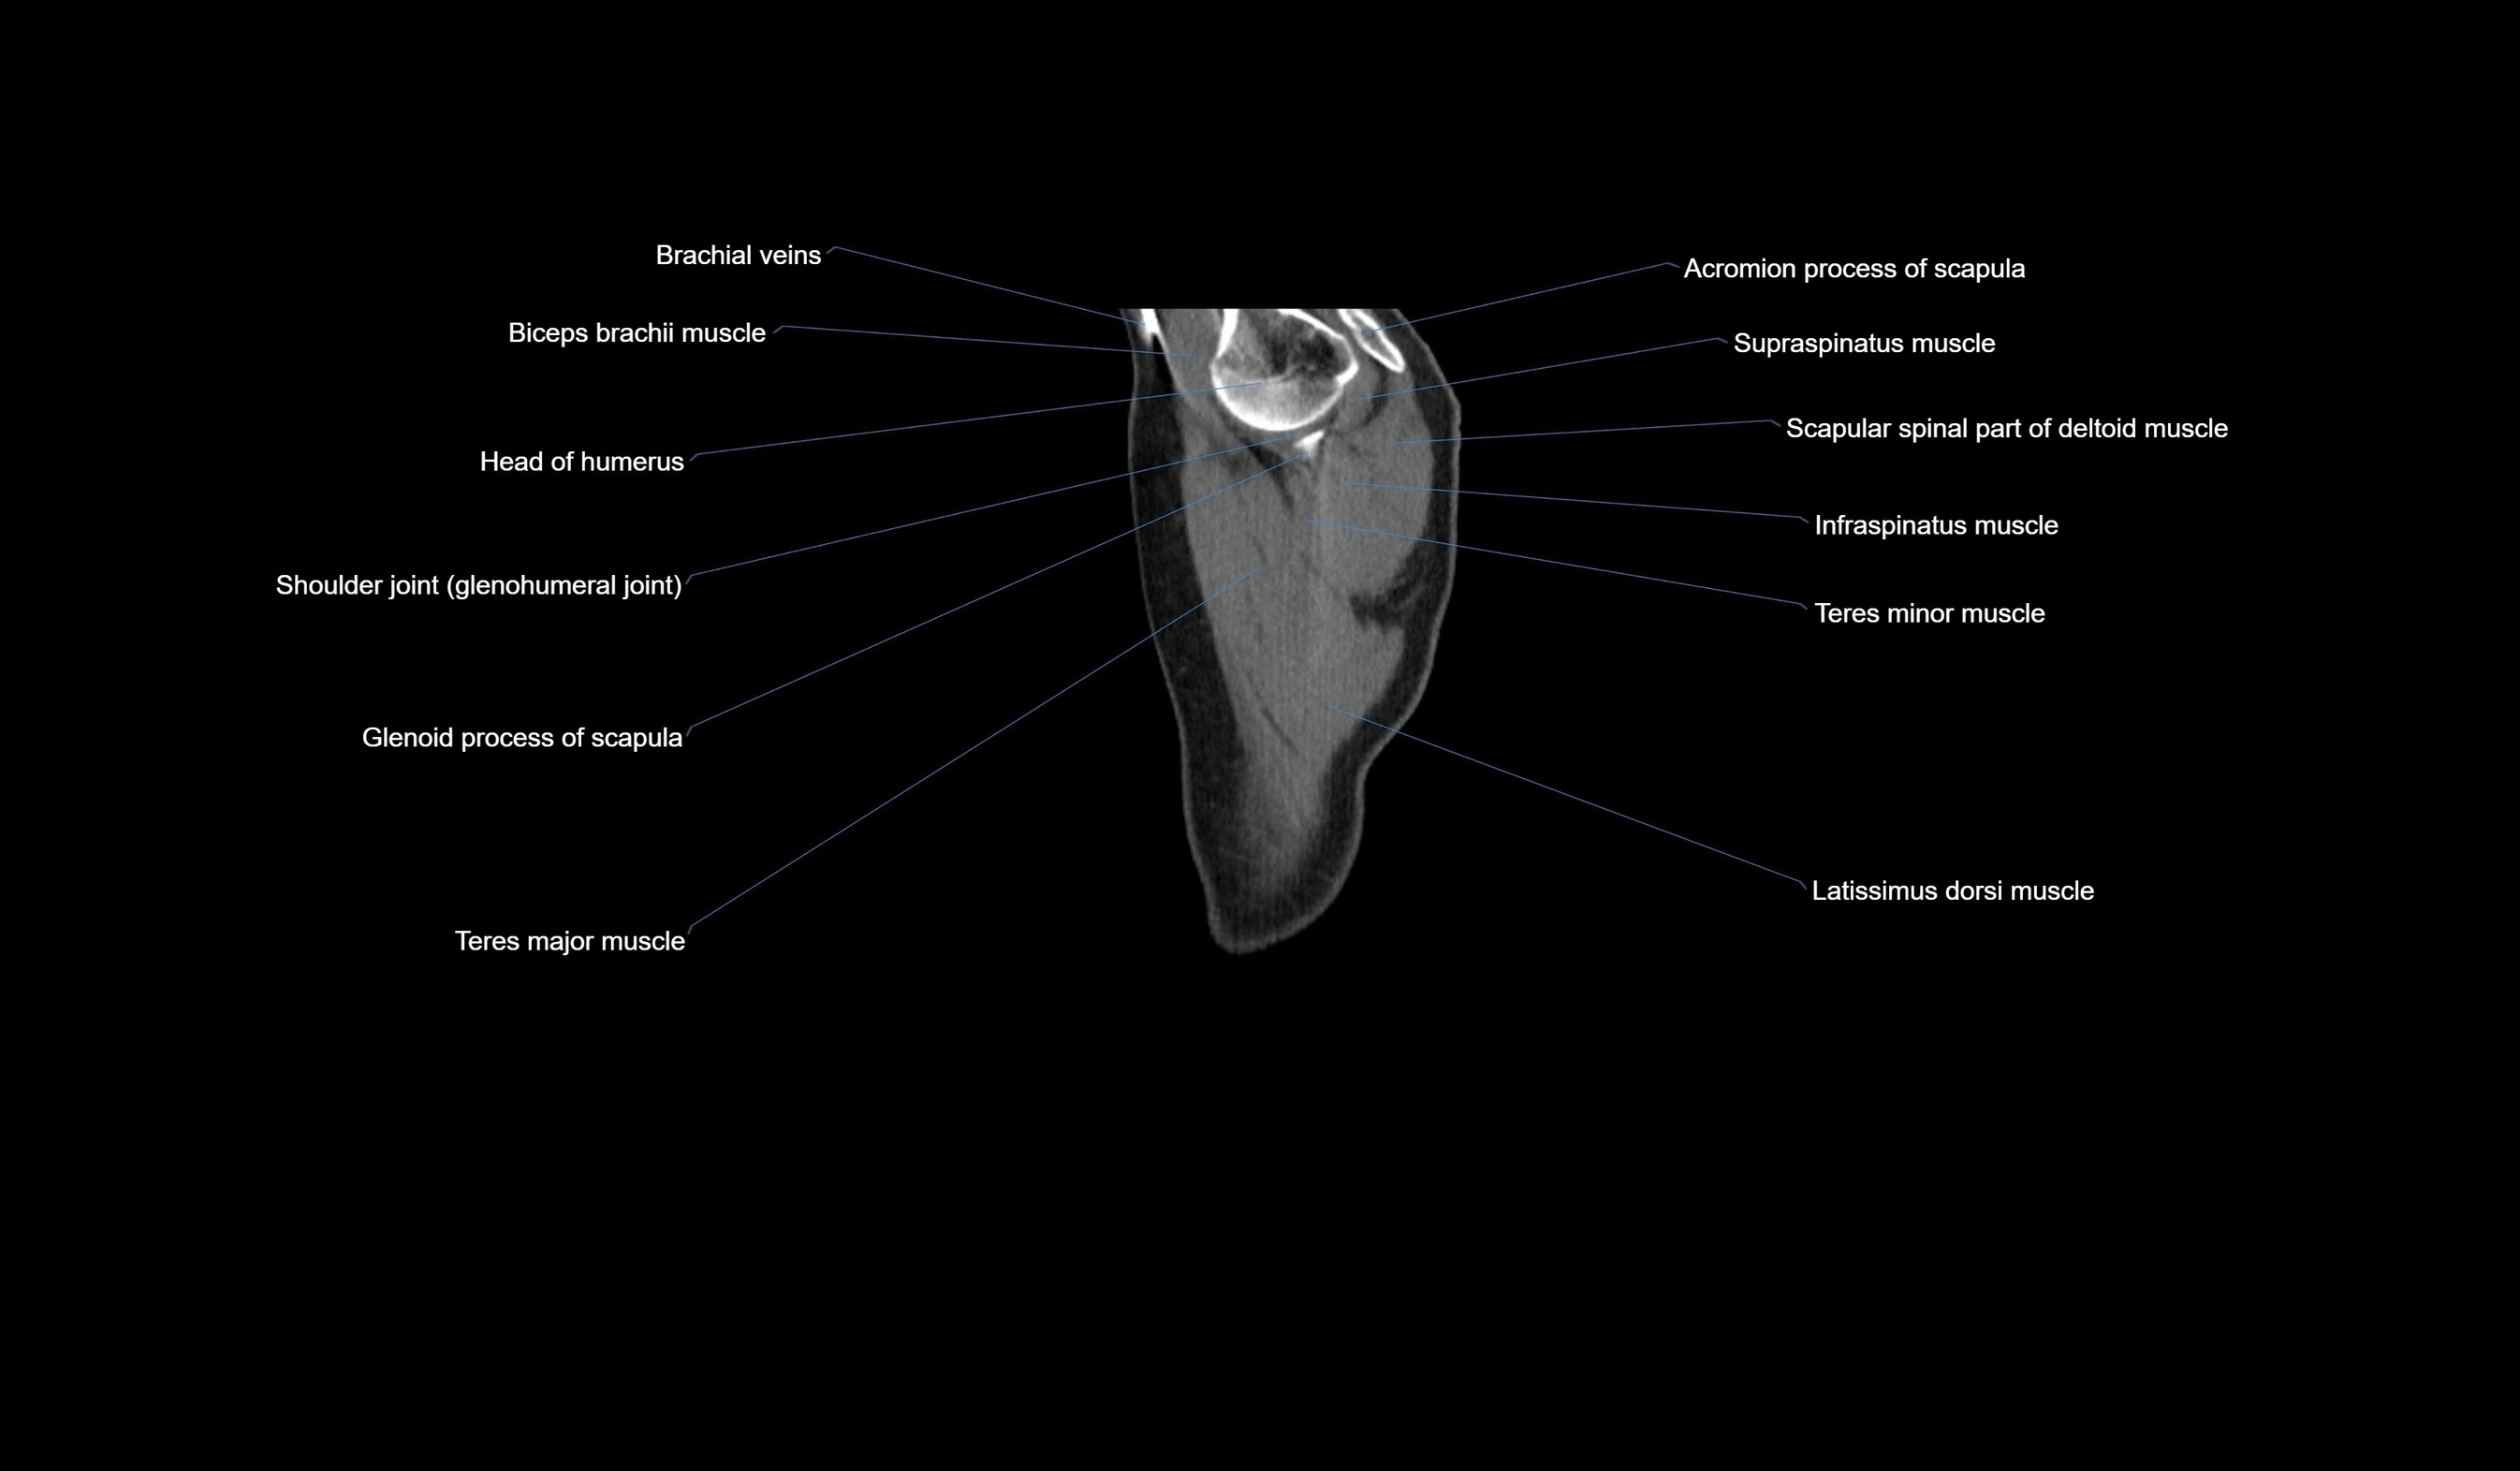

- Biceps brachii muscle

- Brachial veins

- Glenohumeral joint

- Glenoid process of scapula

- Head of humerus

- Infraspinatus muscle

- Latissimus dorsi muscle

- Long head of biceps brachii muscle

- Scapular spinal part of deltoid muscle

- Shoulder joint (glenohumeral joint)

- Subscapularis muscle

- Supraspinatus muscle

- Teres major muscle

- Teres minor muscle